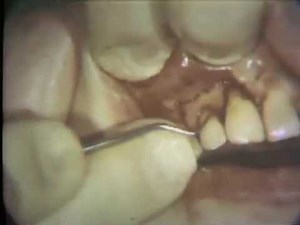

Lateral Sliding Flap

15.8K views

May 15, 2009

YouTube

UMichDent